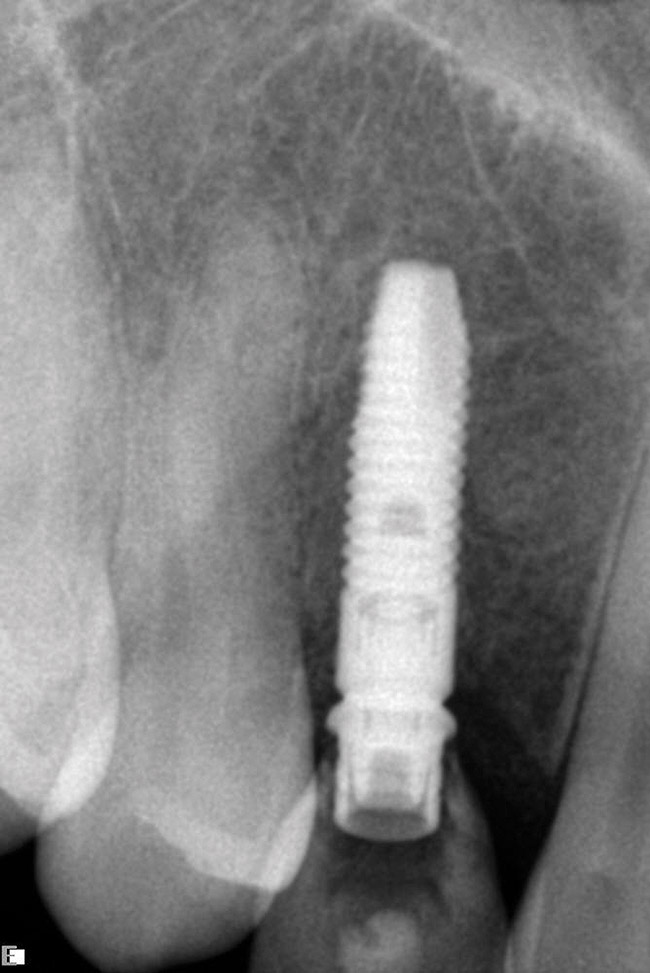

The patient was scanned with a cone beam CT scan while wearing a radiopaque scanning appliance based on her new treatment denture. Horizontal bone augmentation was confirmed radiographically, and both grafted sinuses resulted in satisfactory bone quantity for implant placement. Vertical augmentation was not attempted because of the patient’s unwillingness to forego her removable prosthesis for any period of time. Therefore, shorter implants were treatment-planned, resulting in the placement of eight implants, rather than fewer—such as six—implants, to support a full-arch fixed prosthesis. Because adequate bone and keratinized mucosa were present, a flapless, computer-guided implant insertion was performed (Figure 18). After removal of the surgical guide, placement of all eight implants could be inspected (Figure 19). Post-placement periapical radiographs are shown in Figure 20 and Figure 21.

Figure 20  Post-placement periapical radiographs.

Figure 20

Figure 21  Post-placement periapical radiographs.

Figure 21